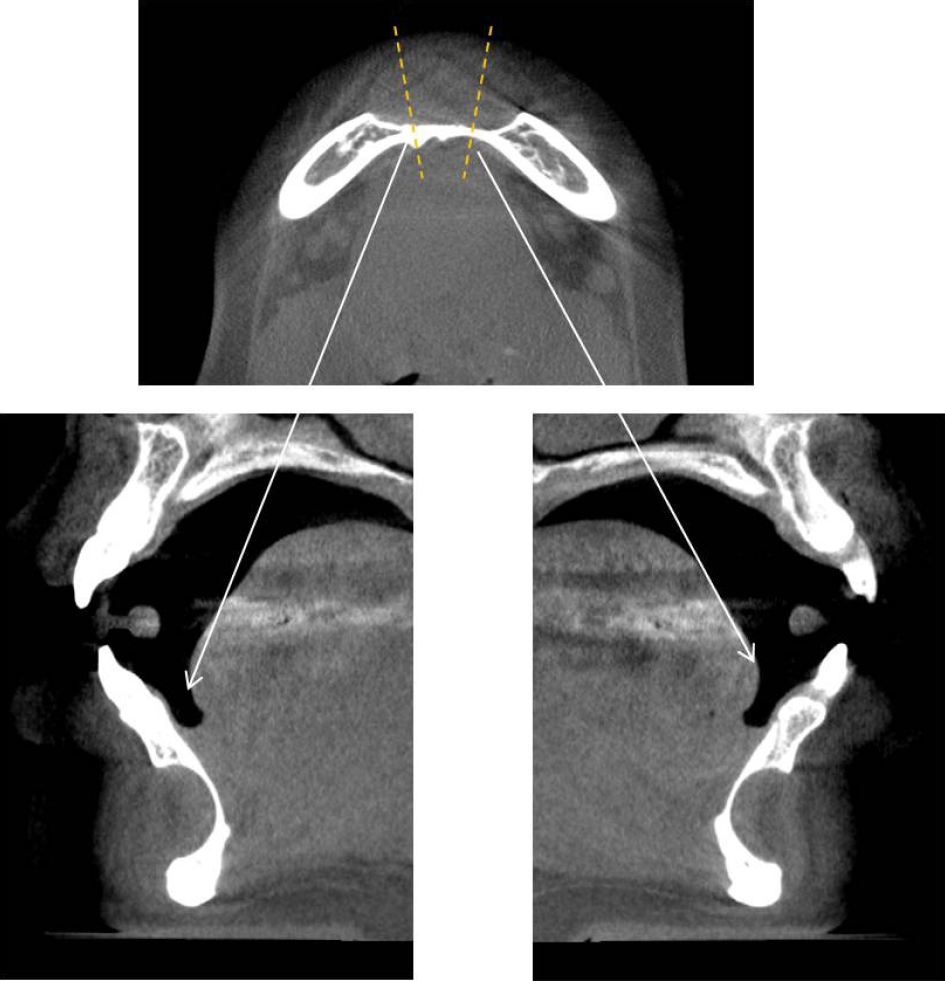

32세 여성 환자의 파노라마방사선영상에서 하악 전치부 낭이 관찰되어, 정확한 진단을 위하여 본원에 의뢰되었다. 특별한 임상증상은 없었다. 파노라마방사선영상에서 하악 우측 제1소구치에서 좌측 제1소구치 치근하방에 경계가 명확하고 피질골성 변연을 가진 타원형의 방사선투과상이 관찰되었다(Fig. 1). 방사선투과상은 해당치아들과는 무관하여 치근단낭이 배제되었고, 단순골낭의 가능성을 염두에 두고 콘빔CT 검사를 시행하였다. 콘빔CT에서 중심성 골내 병소가 아닌 악골의 순측에서 설측으로 함몰된 변연성 병소가 관찰되었다(Fig. 2). 병소의 경계는 매우 평활하였고, 단면상에서는 넓은 접시모양처럼(Fig. 3), 악골 절단면상에서는 반달모양처럼 함몰되어 있었다(Fig. 4). 설측 피질골은 비박되어 있었으나 천공은 관찰되지 않았다. 함몰된 부위는 공기가 아닌 연조직의 방사선투과상으로 채워졌으나, 콘빔CT에서는 대조도가 낮아서 연조직간의 감별이 가능하지 않았다(Fig. 5). 관찰된 턱 끝 부위의 골 함몰이 해부학적 변이인지 아닌지를 감별하기 위하여 환자의 과거 병력을 알아보았다. 환자는 2년 전에 턱 끝 부위에 미용 필러 시술을 받았다고 하였다. 방사선영상소견과 문진결과를 토대로, 미용 필러와 관련된 골흡수를 의심하였다. 이후 외과적으로 미용 필러 제거와 함몰된 부위에 골이식이 시행되었다. 수술 중에 육안으로 남아있는 미용 필러와 작은 석회화 물질들이 확인되었다. 수술 후 생검에서 다핵거대세포와 결절석회화가 관찰되었고, 피부석회화(calcinosis cutis)가 의심된다는 결과를 받았다. 이상의 술 전 검사 및 술 후 소견을 종합하여, 파노라마방사선영상에서 관찰된 방사선투과상은 치성낭이나 해부학적 변이가 아니고 미용 필러에 의한 하악골 순측 골흡수로 최종 진단되었다.

Cone-beam computed tomographic axial view shows a well-circumscribed peripheral depression with smooth borders and a corticated margin.